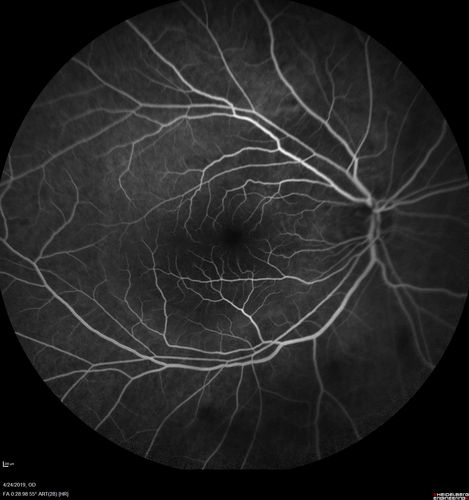

Lung Cancer Metastasis to Right Eye

63 year old female with vision loss for 6 weeks. She had been scheduled for cataract surgery and then a tumor was found. She was ultimately diagnosed with lung cancer. Vision is 20/100

Non Small Cell Lung Cancer - Metastasis to Choroid